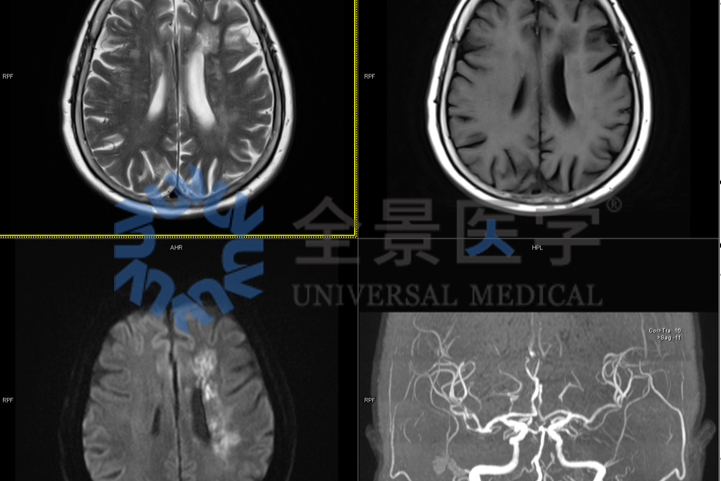

淋巴瘤治疗显成效!PET/CT 见证病灶「大撤退」

淋巴瘤治疗显成效!PET/CT 见证病灶 「大撤退」